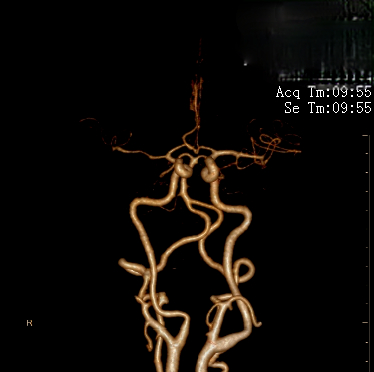

右侧颈内动脉造影显示右侧颈内动脉闭塞。

侧枝代偿差。

术后5月复查CTA显示右侧颈内动脉及大脑中血流通畅。

该病例为颈内动脉C1段远端闭塞,血栓负荷率大,我们采用常规的SWIM技术(支架取栓+抽栓),但是效果不佳,于是改为双支架串联技术取栓,达到mTICI 2b级血管再通效果。

针对本例患者,选择了单纯使用导引导管的双支架串联式释放同时局部并联释放技术,双重支架叠加可以增加支架释放的径向支撑力,同时也增加了支架网丝对血栓的嵌入效应、接触面积和血栓的缠绕能力,快速将血栓拉出体外,提高了开通效率,并最终获得良好开通效果和3个月良好预后。